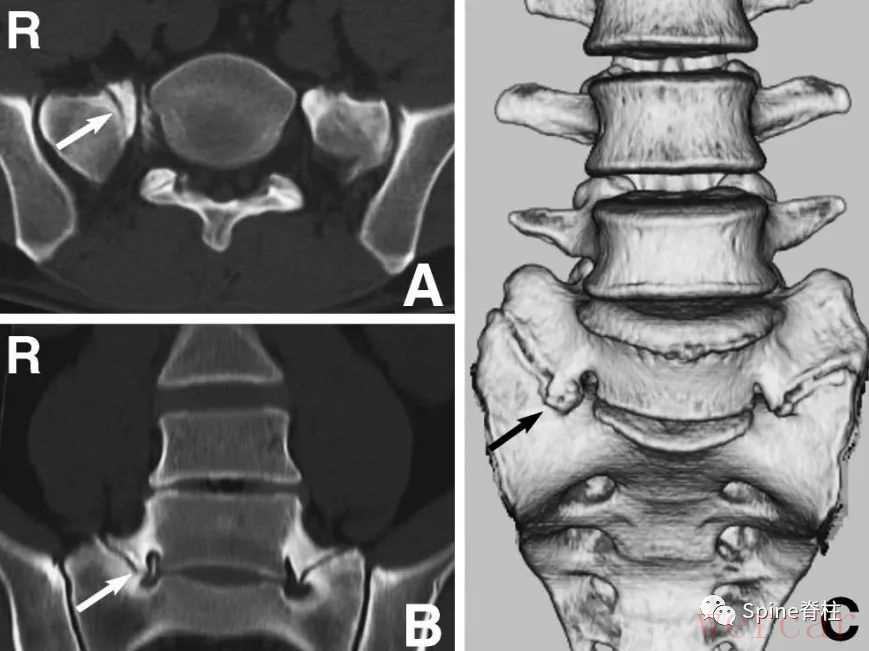

图示:1、2和3分别表示脊神经的入口处、走行处和出口处L5神经除了在入口根、走行根或出口根处受椎间盘影响外,也可在远离椎间孔区域,受L5椎体侧缘骨赘压迫,或在L5肥大的横突与骶翼之间受压迫,引起典型的L5脊神经根病(L5 radiculopathy),从而出现与腰椎间盘突出症相似的下肢放射痛,也有学者称之为远端综合征(Far-out syndrome)或症状性腰骶移行椎(Symptomatic LSTV),又称为Bertolotti 综合征。

图示:确诊为 LSTV IIb型(具体分型详见:你注意过腰5椎体的横突吗?),患者L5神经根右下肢放射痛通过选择性根管造影确诊,增生肥大的横突与骶骨形成的假关节压迫椎间孔外侧远距离处的L5神经。